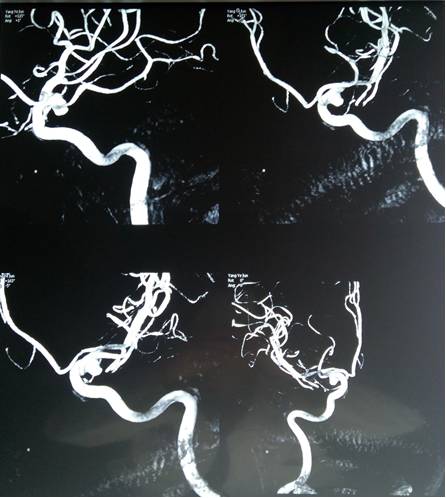

患者术后一般情况良好。术后第一天复查头颅MRA见动脉瘤完全夹闭,未见明显瘤颈残留(图6)。因肾功能不全且MRA复查无明显残留,所以为了减少肾功能损害术后未复查DSA。患者恢复良好,于术后7天出院。

图6. 术后第2天复查MRA见动脉瘤完全夹闭,未见明显瘤颈残留,颈内动脉及后交通动脉未见明显狭窄,A:右侧位;B:前后位。